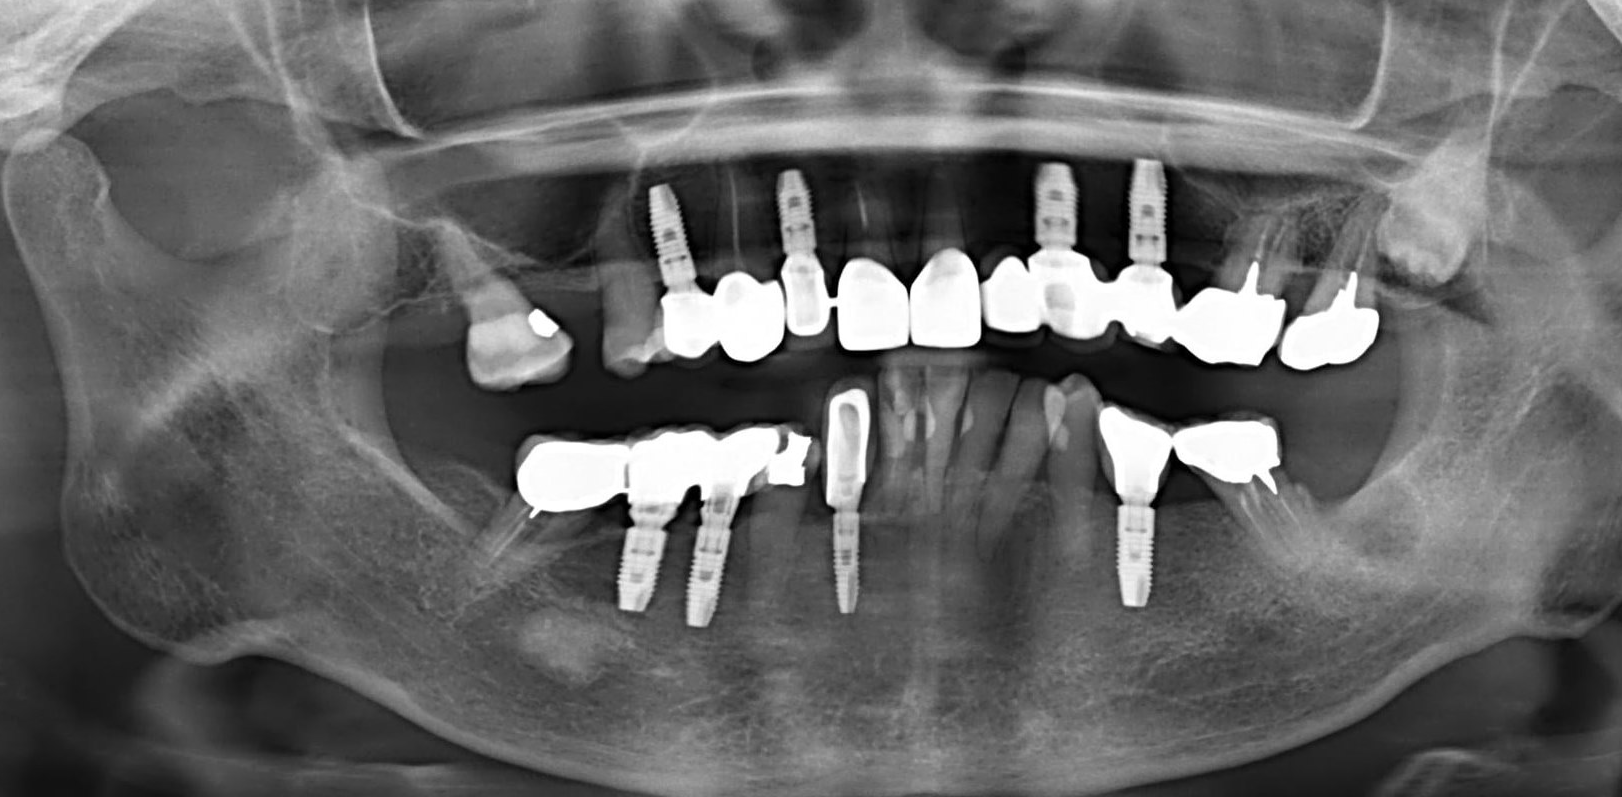

第三版的30年GBR,從261頁增加到340頁。章節也從九章增加到十四章,大致上,增加了前一版沒有的拔牙窩形變、立即植牙、前牙軟硬組織美學、植體周圍炎、補骨併發症。還有減少Bone Block的內容,字型也改成容易閱讀,不易疲勞的襯線體。

●第五章,新增一整章節,整理影響補骨的因素,從植體選擇、植體種植位置、缺損區分類,許多前一版沒有的精美卡通圖,非常詳盡。光是水平骨缺損,就詳細分類了三大項,七小項,挺複雜的。其實說穿了,這邊分這麼多種,好像很難,其實背後的含義,就是將難度區份成不同等級,彼此使用的材料、手術技巧、介入時間與思考,是不一樣的。第六章的植牙時機,也是同樣在ITI Treatment Guide可以看到。

●第八章就是Buser最著名的Early implant placement in the esthetic zone,完整分類風險等級、挑選案例、單顆植體、多顆植體的前牙手術考量。更加入了超過十年的術後追蹤。我認爲Buser在這塊領域的貢獻非凡,是整本書的精華所在。

●第十一章垂直補骨,前一版的作者Massimo Simion,改成了Istvan Urban,果如我2016年判斷的,Istvan Urban已成為垂直補骨的接班人,連主編Buser也這麼認為(笑)。這邊寫的是簡易版,若朋友有興趣詳細的垂直補骨,直接看Urban寫的兩本垂直補骨書即可,我這邊也有第二本Vertical 2心得。但是十一章關於頰側與舌側的皮瓣鬆弛,寫得簡潔扼要,值得詳讀。